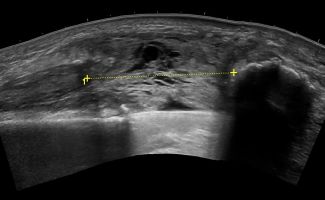

Το Υπερηχογράφημα Γόνατος προσφέρει τη δυνατότητα απεικόνισης παθολογιών στην άρθρωση, τους θυλάκους, τους τένοντες, τους συνδέσμους, τα νεύρα, τα αγγεία και τα μαλακά μόρια της περιοχής του γόνατος.

- Κύστεις Baker

- Δυναμικές δοκιμασίες: Η δυναμική φύση της υπερηχογραφίας είναι ιδιαίτερα χρήσιμη για την διάγνωση και αξιολόγηση παθήσεων του γόνατος, καθώς επιτρέπει την παρακολούθηση της κίνησης του γόνατος σε πραγματικό χρόνο. Αυτή η δυνατότητα εξασφαλίζει την ολοκληρωμένη, λεπτομερή και αξιόπιστη διάγνωση προβλημάτων που μπορεί να πλήττουν την περιοχή του γόνατος.

Το Υπερηχογράφημα Γόνατος αποτελεί μία απλή και ανώδυνη διαδικασία που δεν απαιτεί προετοιμασία από τον ασθενή. Κατά τη διάρκεια της εξέτασης, ο ασθενής ξαπλώνει στο εξεταστικό κρεβάτι και η Ιατρός τοποθετεί ζελέ στο δέρμα της περιοχής και διενεργεί την εξέταση με ηχοβολέα υψηλής ανάλυσης. Με την καθοδήγηση της Ιατρού, ο ασθενής εκτελεί ορισμένες κινήσεις με το πόδι του ώστε να πραγματοποιηθεί η δυναμική αξιολόγηση. Η συνολική διάρκεια της εξέτασης κυμαίνεται στα 30 λεπτά.